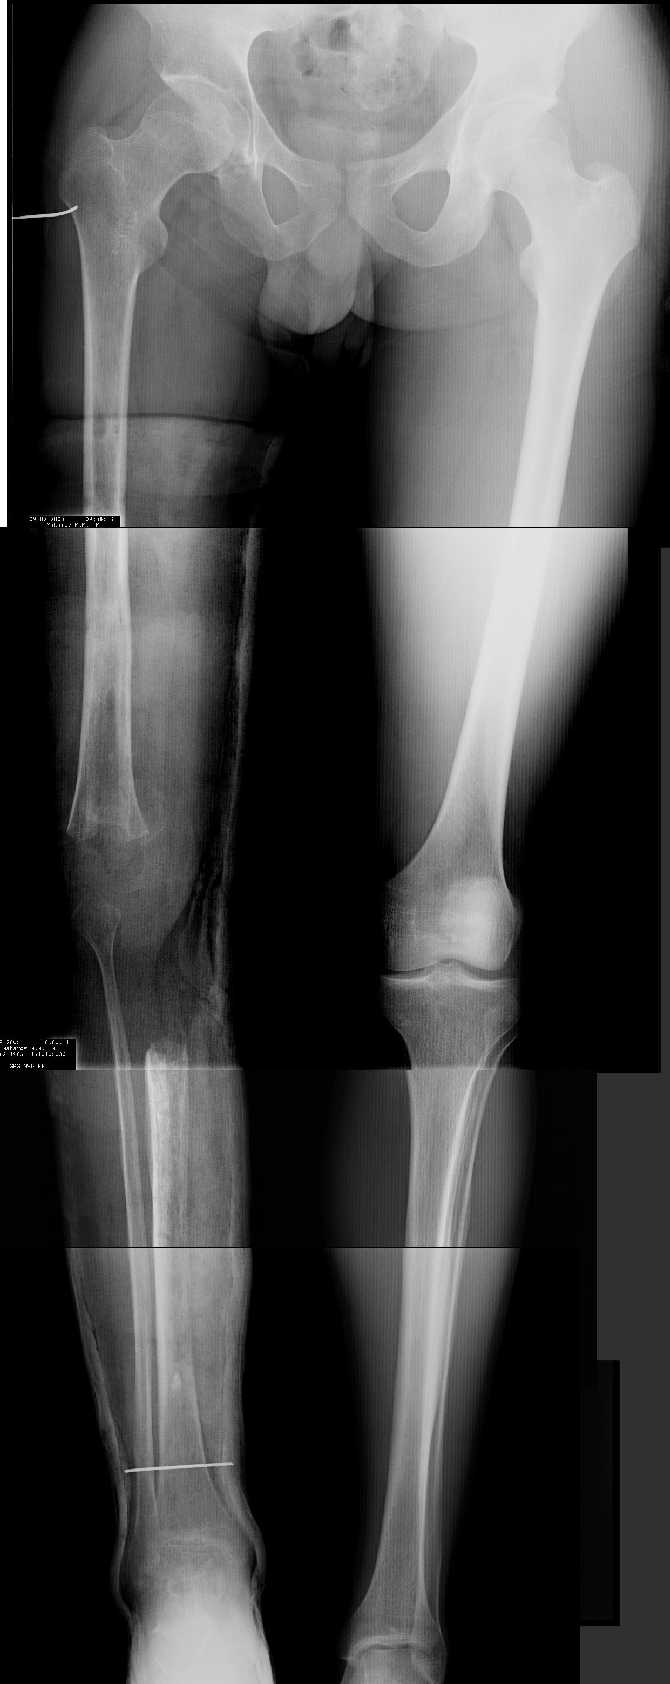

AV> многооскольчатый перелом правой бедреннойљ кости на границе

AV> средней и нижней трети со смещением,

AV> В настоящее время стойкая разгибательная контрактура правого

AV> коленного сустава (сгибание 105-110 гр., разгибание 160-165 гр.),

AV> варусная деформация, болевой синдром.

имеется S-образная деформация бедра на фоне "многооскольчатого

перелома правой бедреннойљ кости на границе средней и нижней трети со смещением"

(хотя "длинные" снимки конечно же не помешали бы...)

Почему же не вмешаться на в/3 голени (вальгизировать)?

По крайней мере это не усугубит контрактуры в коленном суставе но

позволит нормально перераспределить нагрузку...

На представленных снимках эта деформация как раз и не представлена.

1. Иллюстрации - во вложении.

Два бедра после эндопротезирования.

Авторы операции долго думали почему больная хромает.

Сдклали снимок - одна нога короче почти на 3 см.

Здоровый человек и то будет хромать.